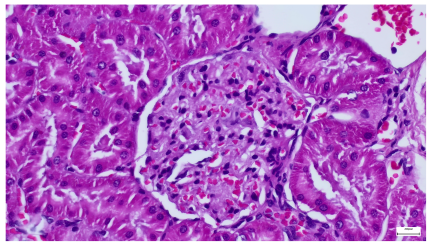

| 4.1. Hematoxylin and Eosin stain, 200× magnification. Normal aspect of the glomerulus, afferent arteriole, efferent arteriole, and normal renal tubules. Control group specimens. | 4.2. Hematoxylin and Eosin stain, 200× magnification. Normal aspect of the juxtaglomerular apparatus. Control group specimens. |

| 4.3. Trichrome Masson stain, 100× magnification, 200 microns scale segment. Arteriole thickening (black), glomerular basal membrane thickening (blue), mesangial cell expansion (yellow), proximal renal tubule basal membrane thickening (green). Group II obese High-Fat-Diet-fed specimens. | 4.4. Hematoxylin and Eosin stain, 200× magnification, 100 microns scale segment. Glomerular congestion and mesangial cell expansion. Group II obese High-Fat-Diet-fed specimens. |